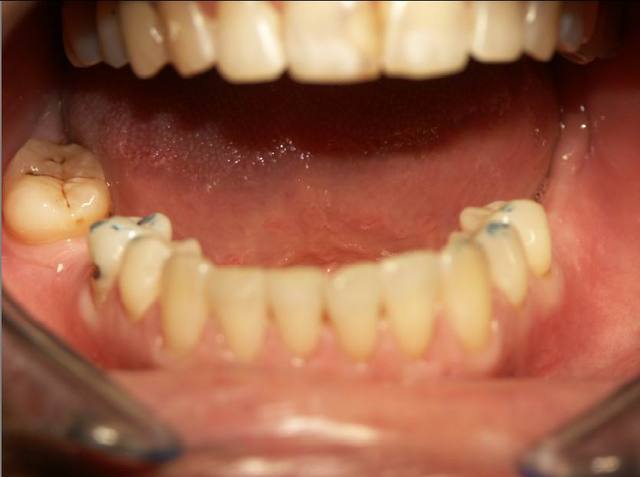

Autre cas .........d occluso.

Pour le cas d occluso ..........

Patiente de 43 ans soufrant de coxo-arthrose handicapante depuis + 10 ans. Douleurs permanente, agravée par la station debout.

Sur avis de son medecin, a refusé de se faire operer suite echec aux traitements medicaux.

1 ere seance de meulages mardi 1/2/05. Disparition de ses douleurs permanentes. Sensation de relachement et de dentente musculaire surtout au niveau des hanches.

2e senace aujourd hui. Pas de recidive au niveau des hanches, mais douleur cervicale et craquement ATM....deviation de la Md à l'ouverture....observable sur la photo 2

Meulages des dents marquées en bleu.

Disparition de la douleur cervicale en fin de meulage.

Persistance de craquement ATM et de deviation de la Md.

Prochaine seance mardi prochain.